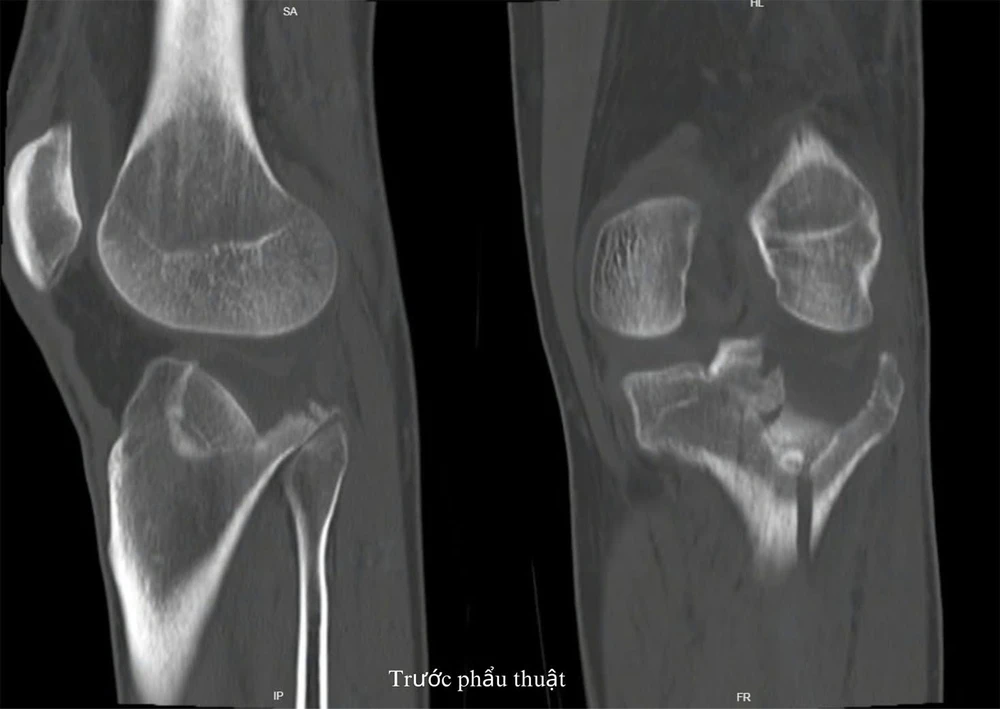

Hình ảnh chẩn đoán gãy mâm chày trước phẫu thuật. Ảnh BVCC

Tại Bệnh viện TP Thủ Đức, bệnh nhân được chẩn đoán gãy mâm chày ngoài phân độ Schatzker III và được tư vấn phương án điều trị phẫu thuật. Ngày 25-3, các bác sĩ tiến hành phẫu thuật cho bệnh nhân.

Bác sĩ Chuyên khoa I, Nguyễn Duy Tài đánh giá, đây là một ca phẫu thuật khó. Về mặt giao tiếp, do bệnh nhân và người nhà không nói được tiếng Việt nên các bác sĩ đã tư vấn bằng tiếng Anh. Về mặt chuyên môn, bệnh nhân bị mâm chày gãy lún, mặt khớp di lệch nhiều. Thêm vào đó, bệnh nhân đến muộn khi gãy xương đã 3 tuần, trong khớp có nhiều mô xơ, ổ gãy đã bắt đầu tạo cal làm dính chặt mảnh gãy.